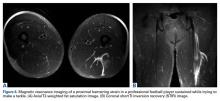

The MRI appearance of hamstring strains shows increased signal within and surrounding the affected muscle belly on T2-weighted imaging as well as the degree of muscle fiber disruption (Figures 6A, 6B). MRI can also be beneficial to confirm the diagnosis of myositis ossificans in chronic cases with a palpable mass.Treatment